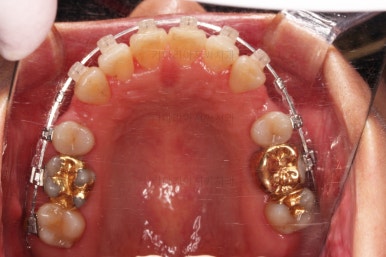

임플란트가 이미 있을 경우

임플란트는 교정이 되지 않습니다.

뼈에 단단히 붙어 있기 때문에 힘을 줘도 원하는 위치로 이동되지 않습니다.

이번 환자분의 경우 임플란트가 어금니 크기보다 작게 제작이 되어 있어서 추후에 교합을 맞추기도 곤란한 상황이었어요.

그래서 교정 후에 임플란트 뿌리 부분은 그대로 사용하고 머리 부분만 재제작 하기로 했습니다.

아래쪽 임플란트는 움직이지 않기 때문에 해당 치아를 기준으로 다른 치아를 모두 셋팅해야 하는 매우 난이도 높은 치료가 진행되었습니다.

임플란트는 크기가 작았으므로 교합을 위해서는 어쩔 수 없이 해당 부위에 틈이 남을 수 밖에 없었고요.

남은 틈은 임플란트 상부 보철을 재제작하면서 조절을 하기로 했습니다.